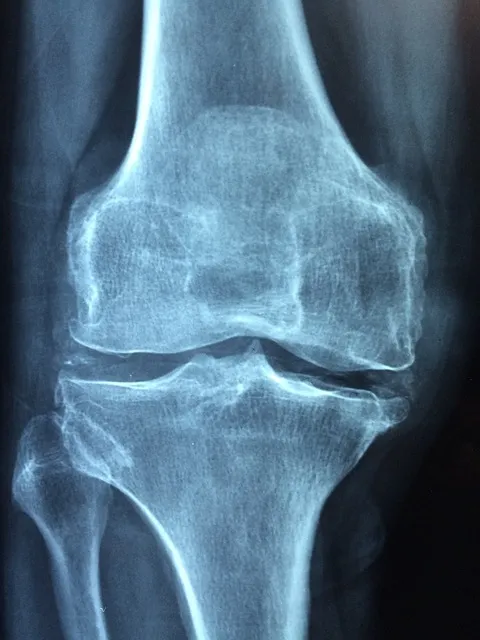

此外,根据影像学检查结果,膝关节炎也可以分为不同的分期。早期膝关节炎患者通常表现为关节间隙变窄和软骨磨损;中期膝关节炎患者则可能出现关节间隙进一步变窄,软骨下骨质增生和囊性变;晚期膝关节炎患者则多表现为关节严重变形,活动受限,甚至需进行关节置换手术。

辅助检查包括X线检查、MRI和超声检查等。X线检查可以显示关节间隙变窄、软骨下骨质增生等特征,是膝关节炎诊断的重要依据。MRI可以显示软骨、骨髓、韧带等结构的细微变化,适用于早期膝关节炎的诊断。超声检查则可以观察关节滑膜、软骨和囊液的变化,有助于诊断急性炎症。

早期膝关节炎患者的主要症状为轻度的关节疼痛和僵硬,尤其是在晨起和长时间不活动后症状较为明显。X线检查可能显示轻度的关节间隙变窄和软骨磨损。这一阶段的治疗主要以非手术治疗为主,如药物治疗、物理治疗和生活方式调整。

中期膝关节炎患者的疼痛明显加重,尤其是在活动后症状更加显著。X线检查可以显示明显的关节间隙变窄,软骨下骨质增生和囊性变。治疗原则仍以非手术治疗为主,但有些患者可能需要手术治疗,如关节镜手术和关节软骨移植等。